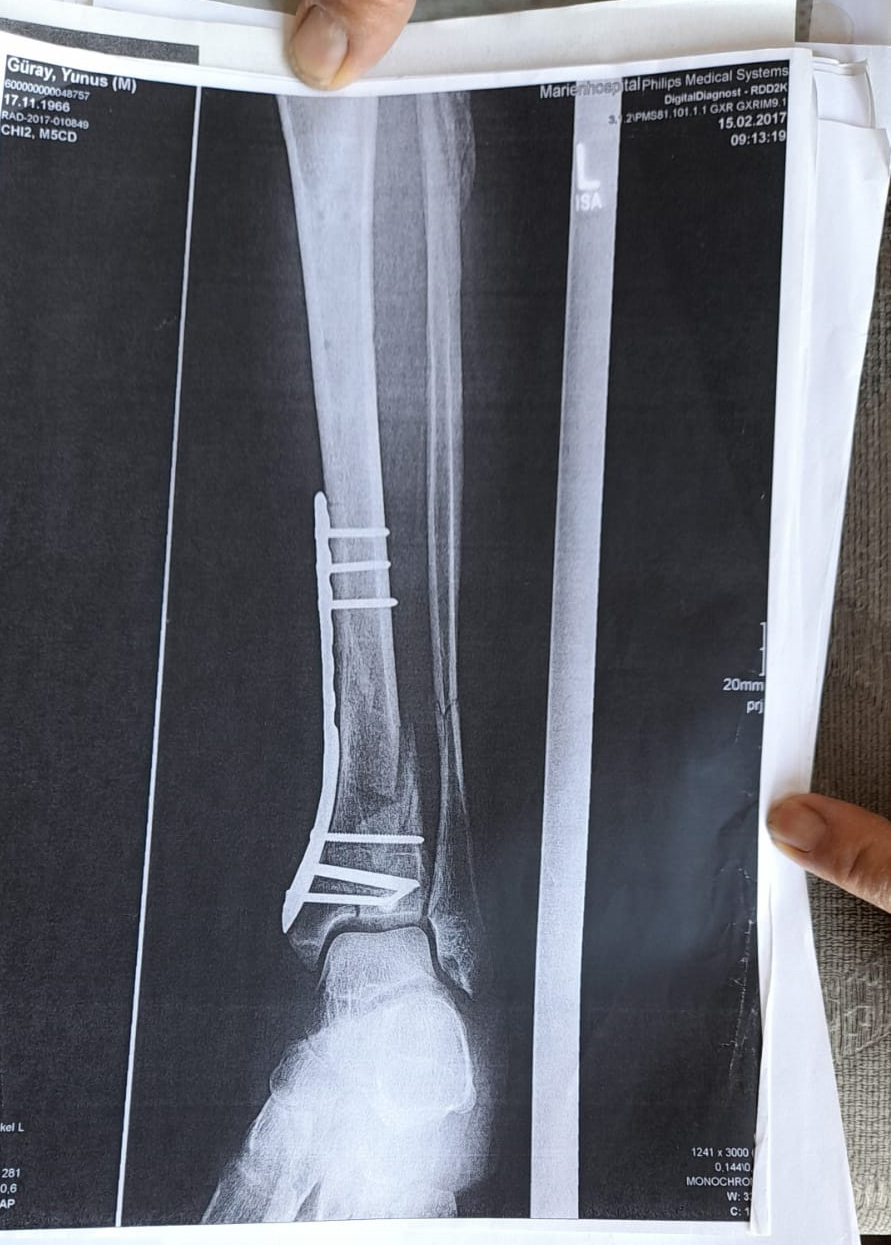

Demir Var Ayağımda, Sakat Bıraktılar

Olay yeriyle ilgili fotoğraf ve görüntüleri mahkemeye sunduklarını kaydeden Güray, “Ömrümü yediler, demir var ayağımda, sakat bıraktılar. Ayağı keseceklerdi neredeyse. Şu an kalıcı sakatlık var. 1 sene kendime gelemedim, 2 haftada bir ameliyata giriyordum. Almanya’da 3 ay hastanede kaldım ve ayağımda yüzde 3’lük engel oluştu” diye konuştu.

Tazminat miktarını düşük bulan Yunus Güray, şunları söyledi: “Benim uçak masrafım sadece 22 bin avro tuttu. 9 yıl oldu, bir tane çukur değildi. Adamlar kazmış, kazmış, bırakmış. Tam merkezde bu olay, hani ormanda bir yerde olur, ‘Tamam benim de hatam var. Gittim de düştüm’ derim. Ama şehrin merkezinde, etrafı çevrili değildi. Yemyeşil alan, gece vaktiydi. Ben mahkemeye verdim, o çukurları 3 ay sonra kapattılar. 6- 7 yerde kazılmış çukurlar vardı. Bir tane değildi. Ayağımda hala demir var. Adil bir karar olmadı.”